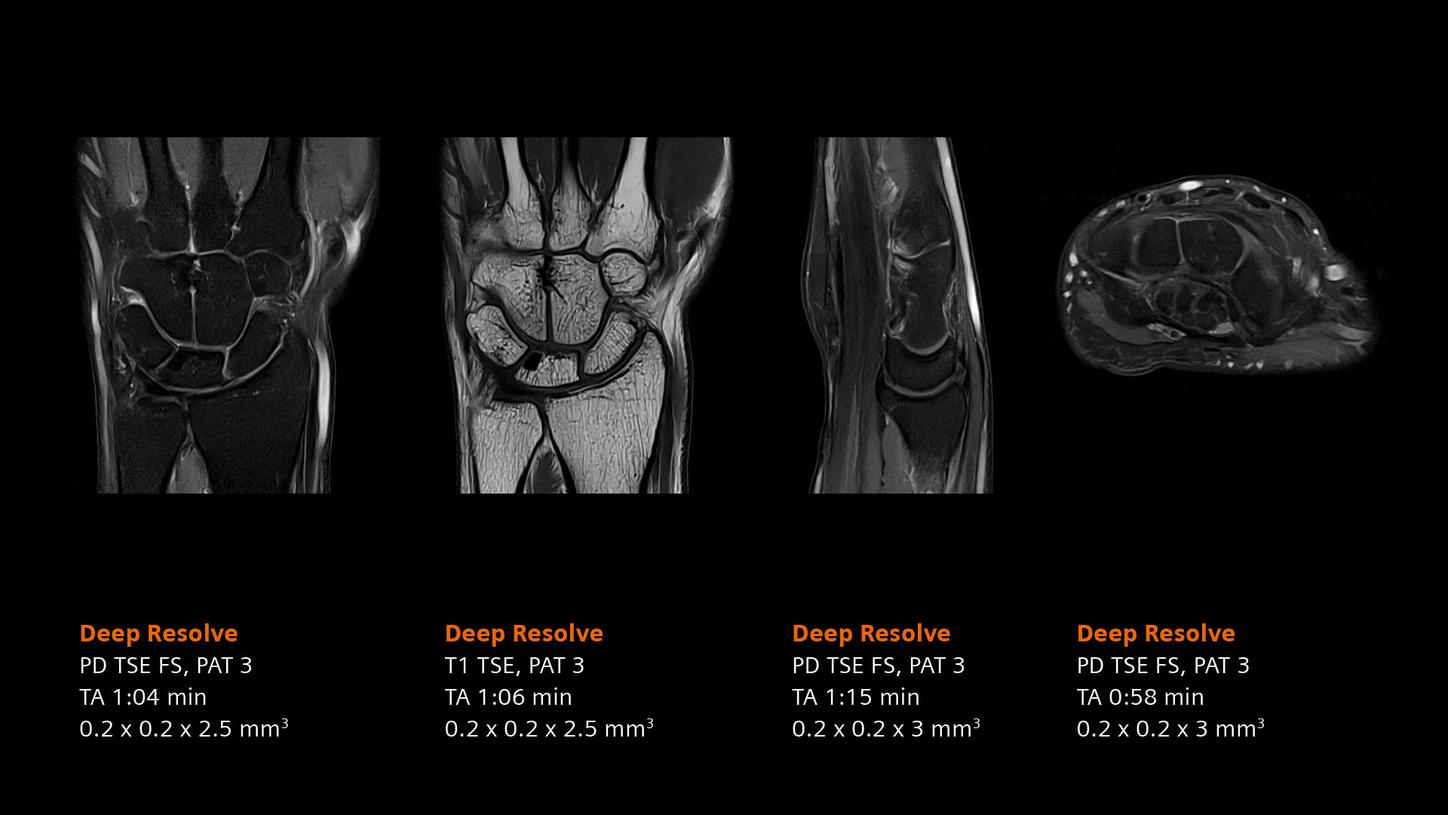

Deep Resolve will be at the forefront of the revolution in MRI acceleration. Deep Resolve will enable our fastest MRI, with images that will have extraordinary clarity, higher clinical productivity, and an even better patient experience. This transformational effect of Deep Resolve is now planned to expand to 3D5, unlocking a new dimension in MRI image resolution and speed.

More about Deep Resolve